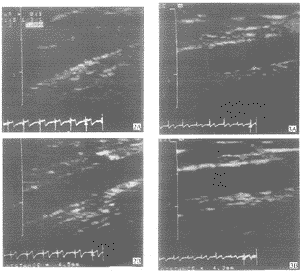

Fig 2 EDD of brachial artery in NP. The diameters are 4.0mm at rest (2A) and 4.5mm during reactive hyperemia (2B).The ΔD% is 12.5%

Fig 3 EDD of brachial artery in PIH. Diameters are 4.1mm at rest (3A) and 4.3mm during reactive hyperemia (3B).

The ΔD% is 4.88%

2.3 妊高征组与正常妊娠组血管扩张程度比较 PIH组充血状态下内径扩张程度(2.08%±2.11%)明显低于NP组(13.04%±3.59%,P<0.001),含服硝酸甘油后PIH组内径扩张程度(14.45%±6.73%)亦明显低于NP组(25.15%±6.98%,P<0.01,见图1~3)。血流量变化率在两组间两种状态下均无显著差异(P>0.05)。